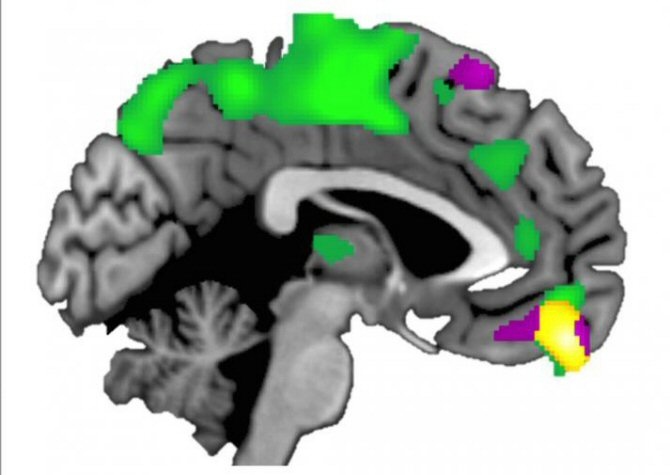

Haas y sus colegas han determinado que el volumen de materia gris es mayor en la corteza prefrontal medial ventral (la región cerebral que sirve para evaluar la recompensa social) de las personas que tienden a confiar mucho en los demás.

![[Img #26730]](upload/img/periodico/img_26730.jpg)